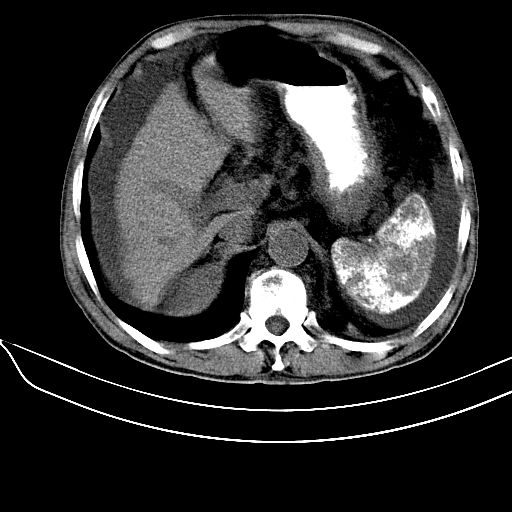

1.肝硬化并腹水,2。肝内多发低密度影,肝内胆管扩张?建议增强。3。胆囊颈部条形高密度影,结石?4。脾脏广泛钙化,门脉主干壁钙化,考虑感染所致。

64岁血管壁钙化也要考虑血吸虫吗?肝硬化肯定。这种脾钙化很像介入术后改变。没见过血吸虫性肝硬化啥样?

长期肝硬化导致的淤血性脾内钙化,超声杂志见过报道.

肝硬化、腹水,脾广泛不均匀高密度影原因?应密切结合病史,病人有没有感染史及造影史?如果都没有可考虑长期肝硬化导致的淤血性脾内钙化。